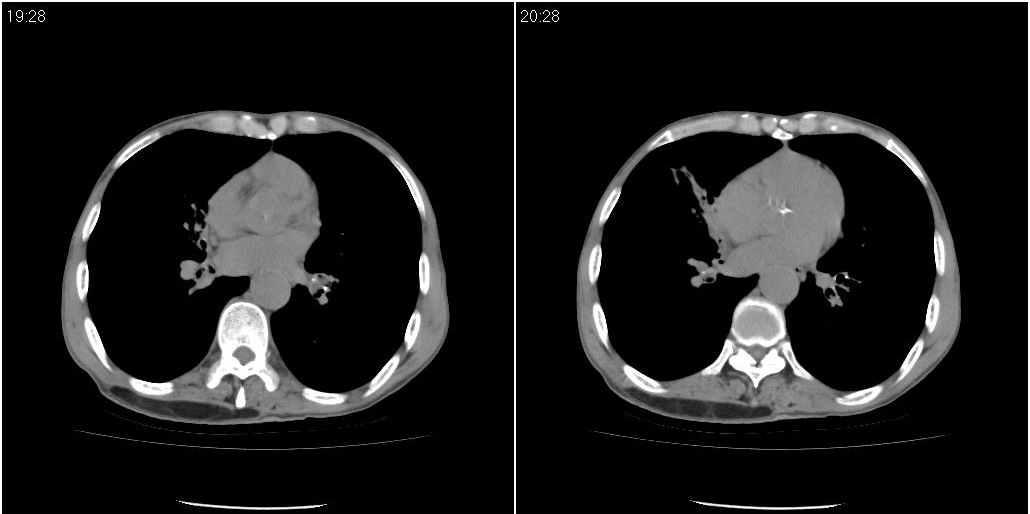

标题: ct增强:

作者: 施明 时间: 2010-3-30 16:07

炎性肿块

右肺中叶阻塞性不张及肺炎,高度怀疑支气管占位,建议纤支镜检查!

考虑右肺中叶感染。左肺下叶支扩。